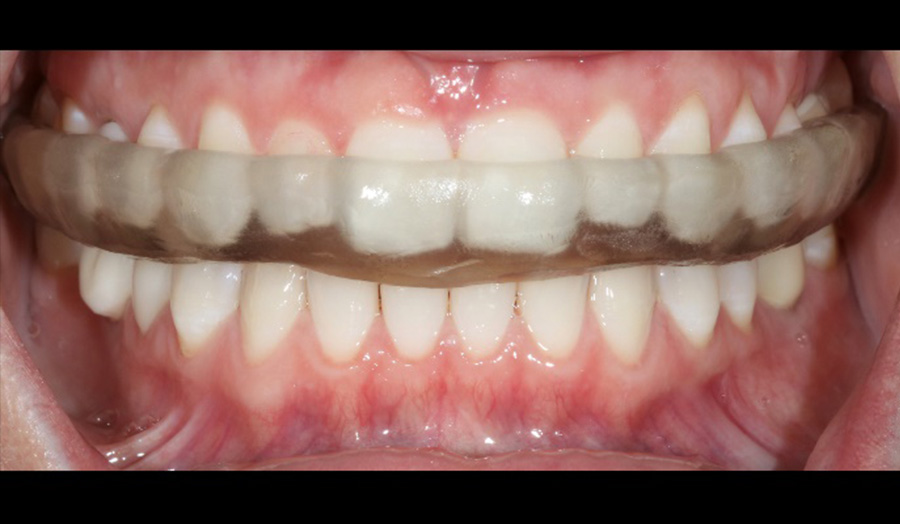

A 34-year-old male presented himself to my practice, with symptoms of nocturnal bruxism and expressed experiencing muscle pain and soreness. We decided that wearing a removable mouth guard at night would minimise wear on his dentition.

Before: Initial oral situation with symptoms of

nocturnal bruxism

After: Detachable 3D-printed splint manufactured with Primeprint Splint material